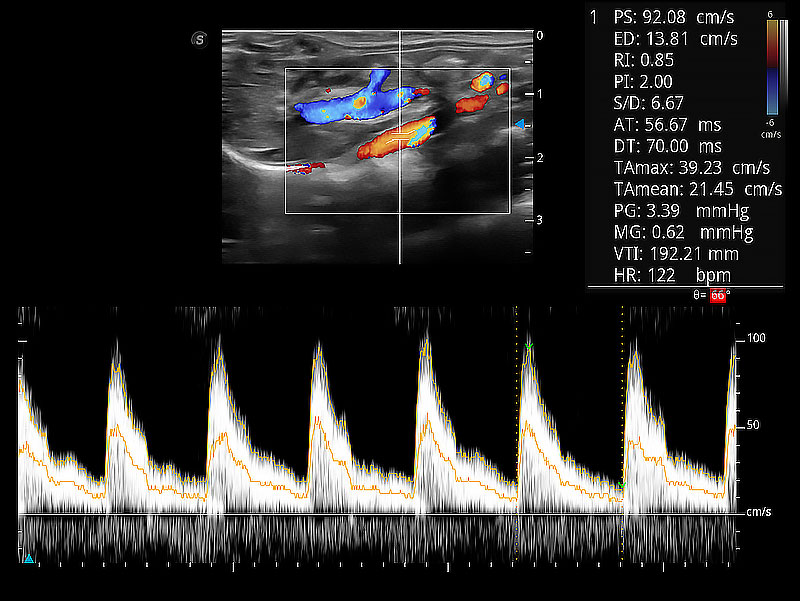

极大提升超低速微细血流的检出能力,同时更精准地滤除软组织和超声信号,为兽用医生提供以往无法通过常规血流获得的疾病诊断信息。

随着取样门位置改变,频谱多普勒包络可进行自动眼踪测量,且可自由配置测量的参数。